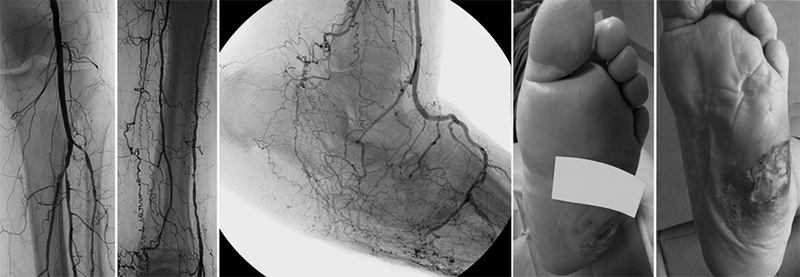

آنژیوگرافی در درمان پای دیابتی اهمیت زیادی دارد، زیرا با ارائه تصویربرداری دقیق از عروق خونی پا، میزان و محل انسداد رگها را مشخص میکند و به پزشک امکان میدهد که بهترین روش بازسازی عروقی را انتخاب کند.

این روش تشخیصی امکان انجام آنژیوپلاستی یا استنتگذاری را همزمان با تشخیص فراهم میآورد که میتواند روند بهبود زخم را تسریع کند.

آیا با وجود زخم پای دیابتی میتوان آنژیوگرافی انجام داد؟ ?

بله! در واقع آنژیوگرافی یکی از مهمترین روشهای تشخیصی برای بررسی عروق پا در بیماران دیابتی است. پزشک محل زخم را با پانسمان مخصوص میپوشاند.

احتمال موفقیت چقدر است؟ ?

در ۷۰-۸۰% موارد نتیجه مطلوب است

عوامل مؤثر:

شدت گرفتگی عروق

کنترل قند خون

مراقبتهای بعد از عمل

وضعیت زخم